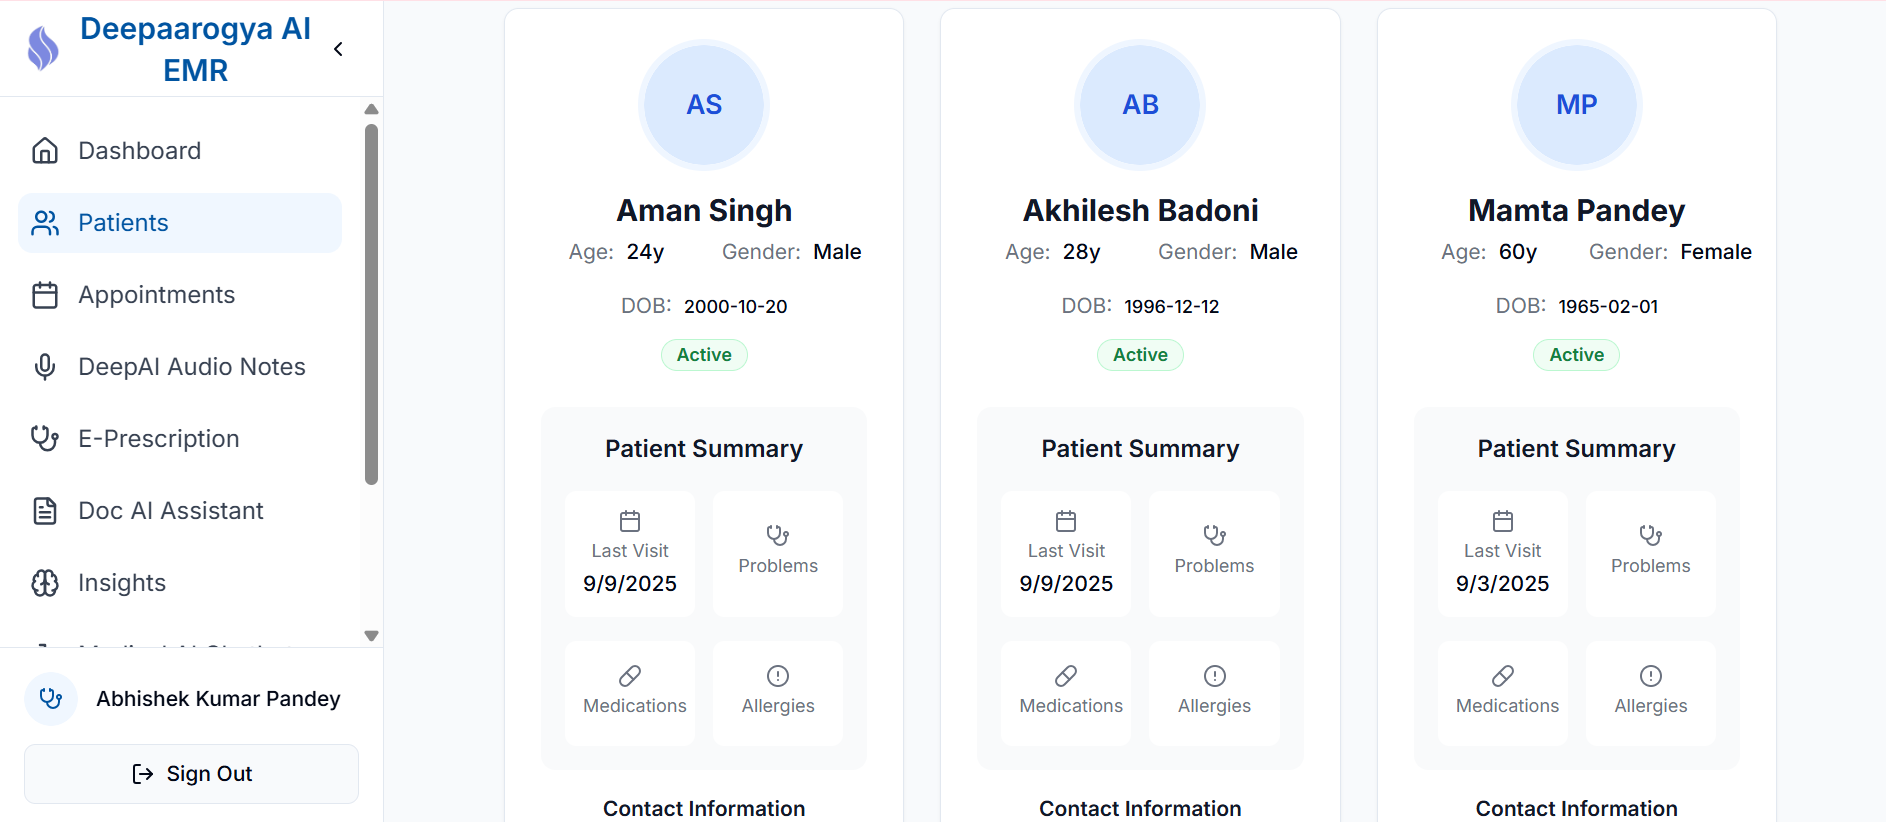

Smart Medical Records & Workflows

AI can also read and summarise medical histories, organise records, or even generate summaries of a patient’s condition — saving doctors hours of administrative work daily.

Electronic Medical Records (EMR)